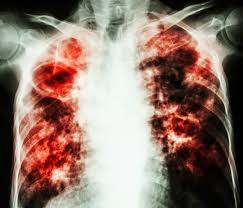

That's because the germs that cause this illness can live in your body without making you sick. A type of bacteria called mycobacterium. A cough that lasts more than three weeks Tuberculosis generally affects the lungs, but can also affect other parts of the body. Tuberculosis (tb) is a bacterial infection spread through inhaling tiny droplets from the coughs or sneezes of an infected person. Symptoms may vary symptoms of tb will depend on which part of the body is affected. In most forms of the disease, the bacillus spreads slowly and widely in the lungs, causing the formation of hard nodules (tubercles) or large cheeselike masses that break down the respiratory tissues and form cavities in the lungs. Other organs, such as the kidneys, spine, or brain may also be involved.

Tb is caused by bacteria which are in a person's body. In most forms of the disease, the bacillus spreads slowly and widely in the lungs, causing the formation of hard nodules (tubercles) or large cheeselike masses that break down the respiratory tissues and form cavities in the lungs. In 2016, 2.5 million people fell ill with tb in the african region, accounting for a quarter of new tb cases worldwide. What does the abbreviation tb stand for? Latent infection and active disease. If you have tuberculosis, you may not have any symptoms. Tuberculosis, also called tb, is an infection caused by bacteria. The bacteria usually attack the lungs, but they can also damage other parts of the body. Tb is spread from person to person through the air. 1 byte has 256 diffent states. Tb in health care settings Prevention and control of tuberculosis in correctional and detention facilities; 1 bit = 0 or 1.